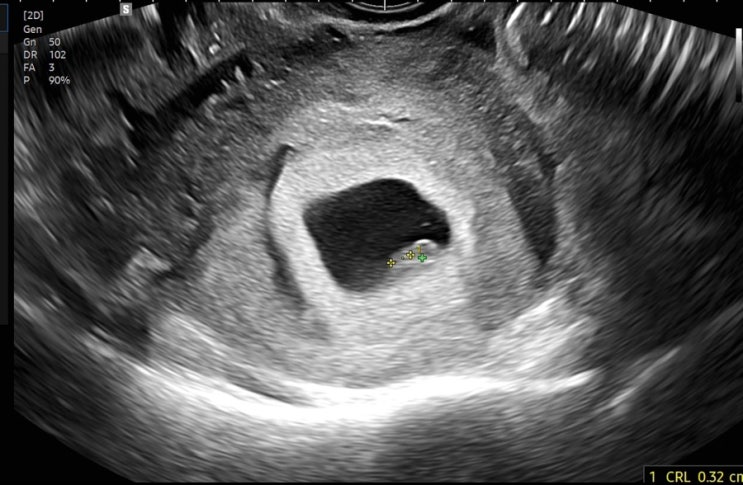

임신 7,8주차 / 여전한 입덧과 환도선다 그리고 태아보험 가입까지 완료

7주차 증상 - 입덧 시간이 지날수록 점점 더 심해지는 입덧 ㅜㅜ 다행히(?) 토덧은 아니고 울렁덧이다 5/17...